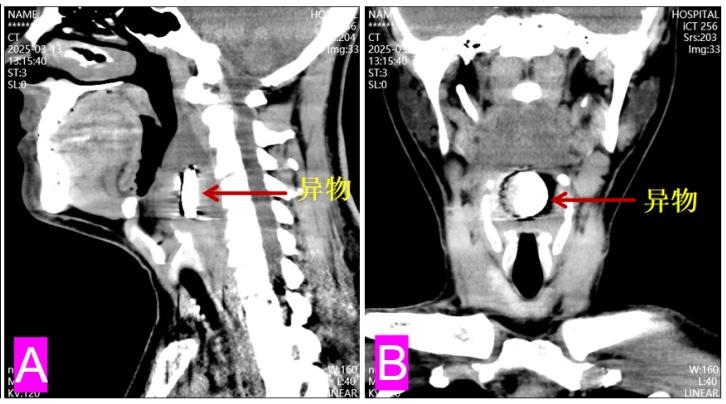

接诊的蔡谦教授团队通过高清喉镜发现端倪——患者咽后壁明显隆起,“拦”在食道入口及声门上缘三分之一,而颈部CT显示下咽部卡着圆形异物,“看起来像一个啤酒瓶盖”。

“临床中误吞异物的情况虽已司空见惯,但如此大的啤酒瓶盖滞留咽喉一年未被发现实属罕见。我们知道,啤酒瓶盖边缘锋利如刀,长期摩擦可能导致黏膜溃烂、深部感染甚至气道压迫。”蔡谦教授用手术影像向记者解释,由于异物被肉芽组织包裹形成“保护壳”,普通检查难以发现,但这个异物却可能引发致命危险。